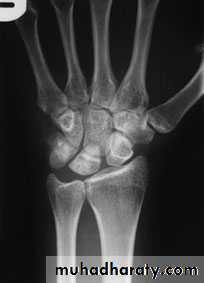

KIENBOCK’S DISEASE

a form of ischaemic necrosis, probably due to chronic stress or injury

Pathology:the pathological changes proceed in four stages

Clinical features:

Imaging:

Radioscintigraphy may reveal

increased activity

X-rays

MRI

Treatment

OPERATIVE TREATMENT

pedicled bone graft

shortening the radius

replacement by a silicone prosthesis

intercarpal fusion or excision of the proximal row of the carpus

radio-carpal arthrodesis

Wrist replacement